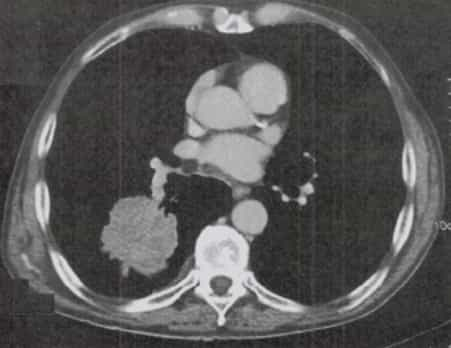

Cáncer Pulmonar de Células No Pequeñas (CPCNP)

El CPCNP constituye una neoplasia maligna originada en el epitelio respiratorio (bronquios, bronquiolos y alvéolos), representando aproximadamente el 80-85% de todos los casos de cáncer pulmonar. Se caracteriza por su heterogeneidad histológica y comportamiento clínico variable, con subtipos que incluyen adenocarcinoma, carcinoma escamoso y carcinoma de células grandes.